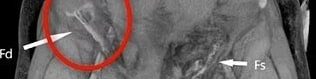

Depois de tratado, os médicos o levaram para fazer uma tomografia computadorizada que apontou onde estava o testículo deslocado. Foi necessária uma cirurgia de 1h30 para que o órgãos fosse colocado de volta ao lugar de origem.